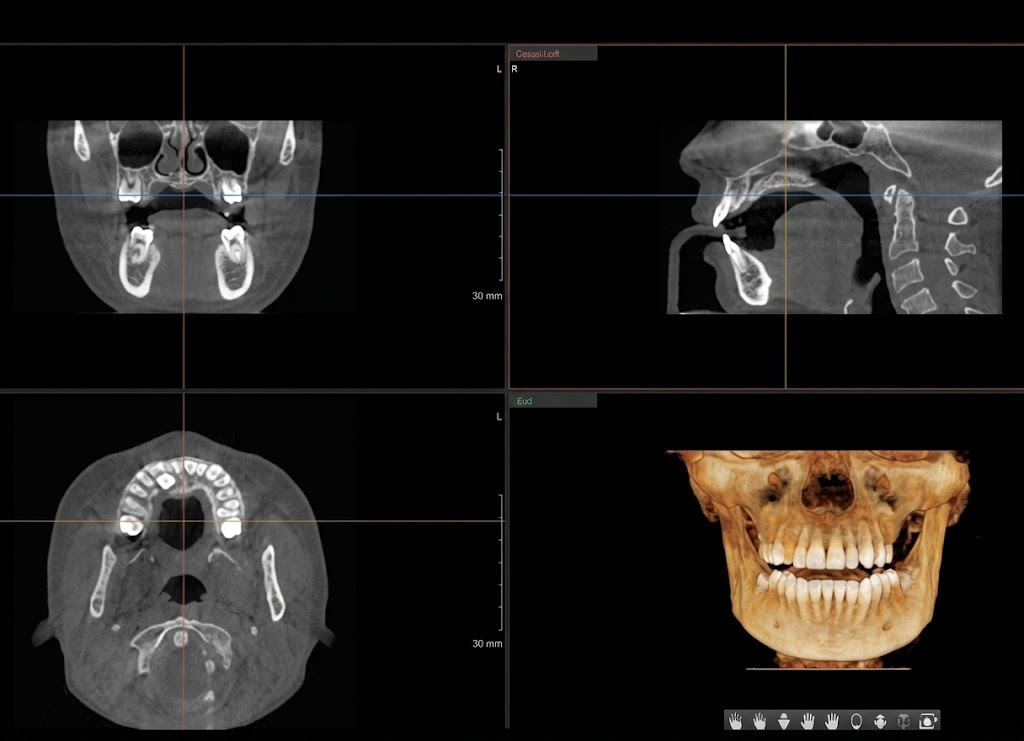

數位精密診斷

以3D CT與口腔掃描器精密診斷後,制訂個人化手術計畫,導出最佳結果。

3D CT 口腔掃描器

精密檢查

3D CT攝影及口腔分析

精密檢查及CT攝影

專科醫師親自確認口腔狀態,透過3D CT攝影精密分析骨組織、神經位置等。同時確認患者的全身健康狀態,為安全手術做好準備。

3D CT精密攝影

骨組織分析

神經位置確認